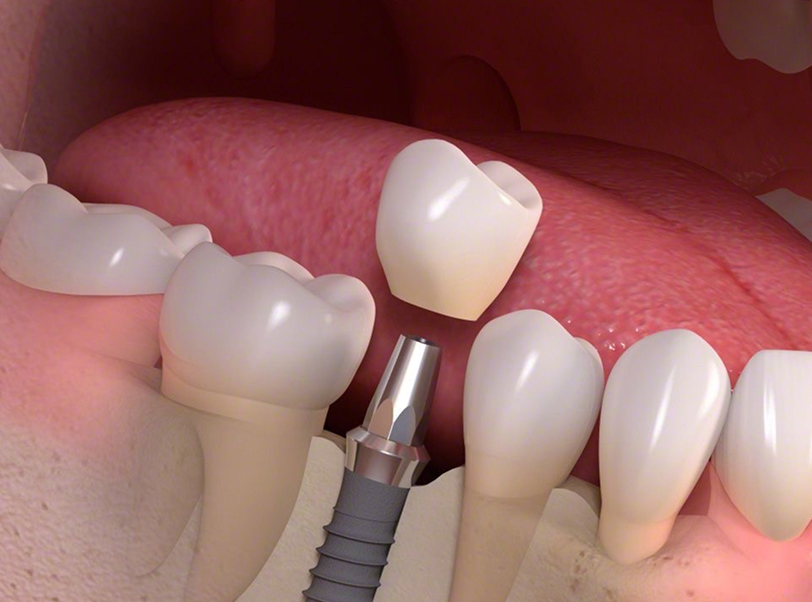

Implantes planejados para integrar estética, função e saúde.

A implantodontia moderna vai além de repor dentes ausentes — ela integra ciência, tecnologia e visão estética para reconstruir sorrisos com naturalidade e estabilidade a longo prazo.

Avaliação tridimensional e planejamento digital completo, garantindo precisão cirúrgica e escolha ideal do tipo de implante;

Protocolos minimamente invasivos, que reduzem edema e aceleram o processo de cicatrização;

Estratégias personalizadas de reabilitação, contemplando implantes unitários, múltiplos ou protocolos totais, sempre priorizando conforto, estética e funcionalidade.